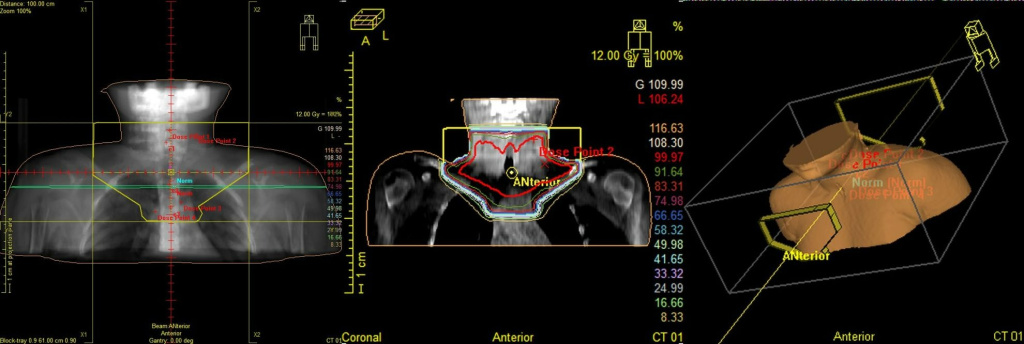

После химиотерапии проводится лучевая терапия (облучение) пораженных зон. Лучевая терапия должна начинаться в течение 14 дней от окончания химиотерапии при нормальных показателях крови.

Завершающим этапом лечения лимфомы Ходжкина является облучение всех пораженных зон лимфатических узлов. Как правило, лучевую терапию начинают через 2 недели после окончания лекарственной терапии при нормализации показателей крови.

Доза облучения зависит от полноты ремиссии после лекарственной терапии: при достижении полной ремиссии (исчезновение всех клинических и радиологических признаков заболевания) в лимфатической зоне по данным ПЭТ-КТ доза облучения составляет 20 Гр. Если размер опухоли после полихимиотерапии уменьшился на 75% и более от первоначальной опухоли и/или отмечается снижение гиперфиксации РФП по ПЭТ-КТ до 2-3 по Deauville, то доза облучения составляет 25 Гр. При уменьшении опухолевых образований менее чем на 75% и/или сохранении гиперфиксации РФП по ПЭТ-КТ 4-5 по Deauville, то дозу облучения увеличивают до 30 Гр.

Рис.5 План лучевого лечения. Пациент И., 4 года 6 мес. Лимфома Ходжкина IIст. с поражением шейных, надключичных, подключичных л/у слева, вилочковой железы, носоглотки. Состояние после 4 курсов курсов ПХТ, ремиссия. Облучение шейно-над-подключичных л/у слева с консолидирующей целью, СОД 20 Гр.